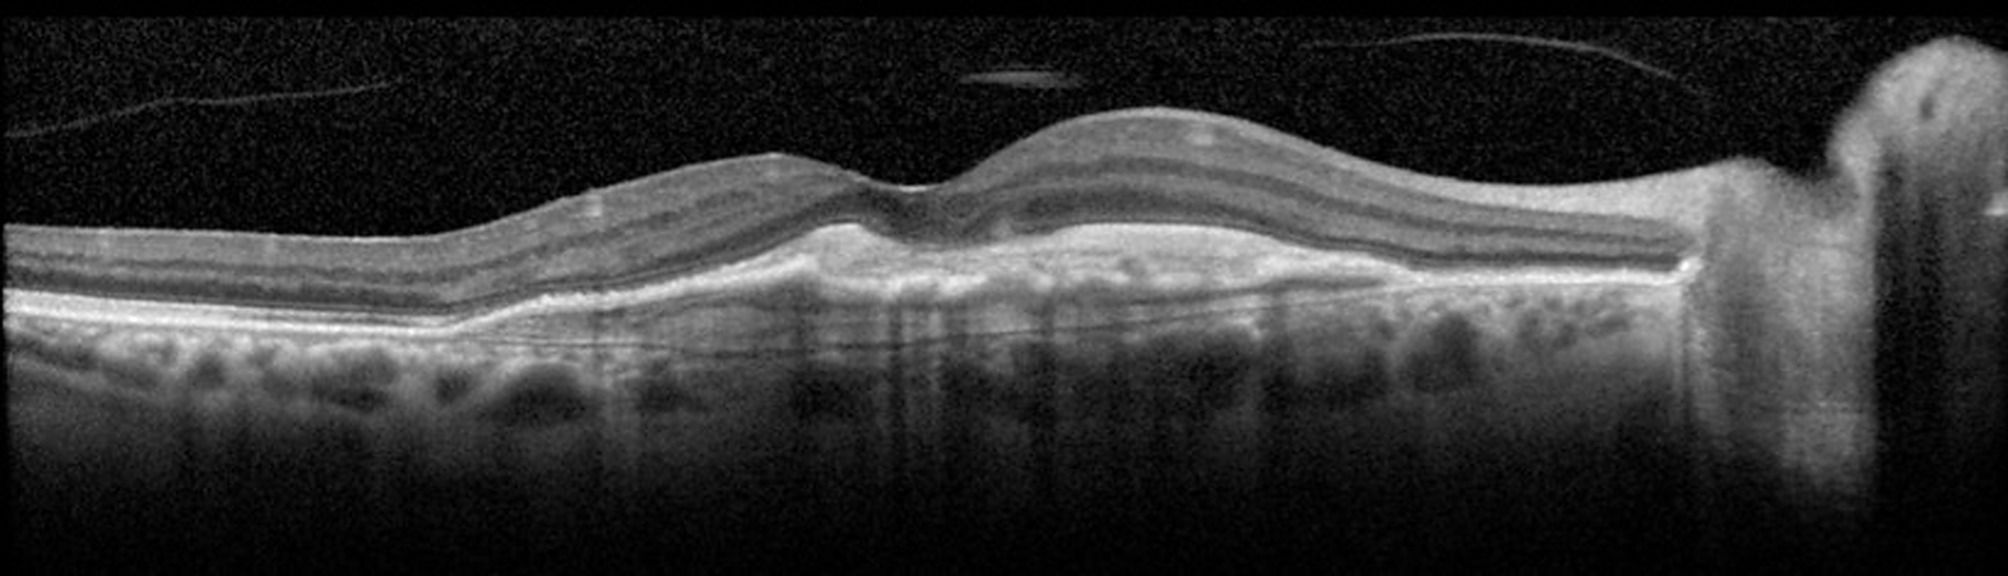

Examens complémentaires : OCT dans la DMLA, Pré-requis en OCT-A,  OCT-A dans la DMLA et CV dans le glaucome

Les examens complémentaires en ophtalmologie ont considérablement évolué. Ils sont devenus indispensables au diagnostic et au suivi des patients, que ce soit dans la dégénérescence maculaire liée à l’âge DMLA ou le glaucome.

Afin de garantir une prise en charge optimale, nous allons détailler dans cette formation comment réaliser un examen de qualité et s’assurer de sa fiabilité, aussi bien pour les champs visuels automatisés, la tomographie en cohérence optique que l’OCT-Angiographie.

Analyser le diagnostic et le suivi des patients en OCT, OCT-A et champ visuel